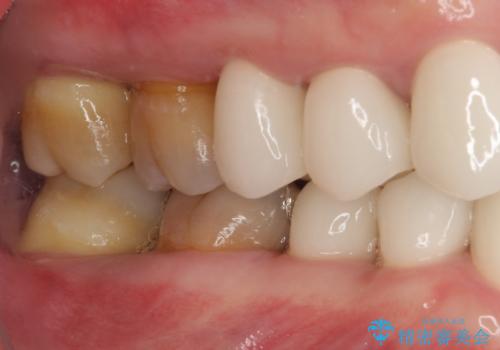

上下ともに前歯のセラミッククラウンによる補綴治療を希望されていましたが、下顎前歯は叢生が強いため、補綴治療前に部分矯正を行って歯列を整えた上で、補綴治療を行うこととしました。

臼歯部には歯周ポケットのある箇所が散見されましたが、まずは前歯を治療したいとのことで、治療を進めました。

ディープバイトにより臼歯部に負担のかかる咬合であったので、補綴治療後には、矯正治療の後戻り防止もかねて、睡眠時にマウスピースを装着するように指示しました。